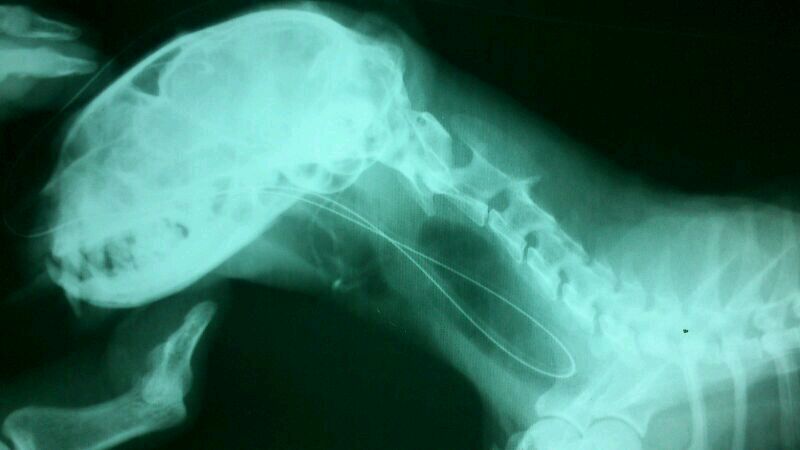

預計鼻胃管餵插管,插管後的x光檢查後發現鼻胃管無法進入食道

轉診其他醫院確診沾黏,建議安樂死

愛心媽媽不忍,自費帶至其他醫院預計進行食道切除重建手術